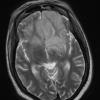

Mucormycosis - Zygomycosis